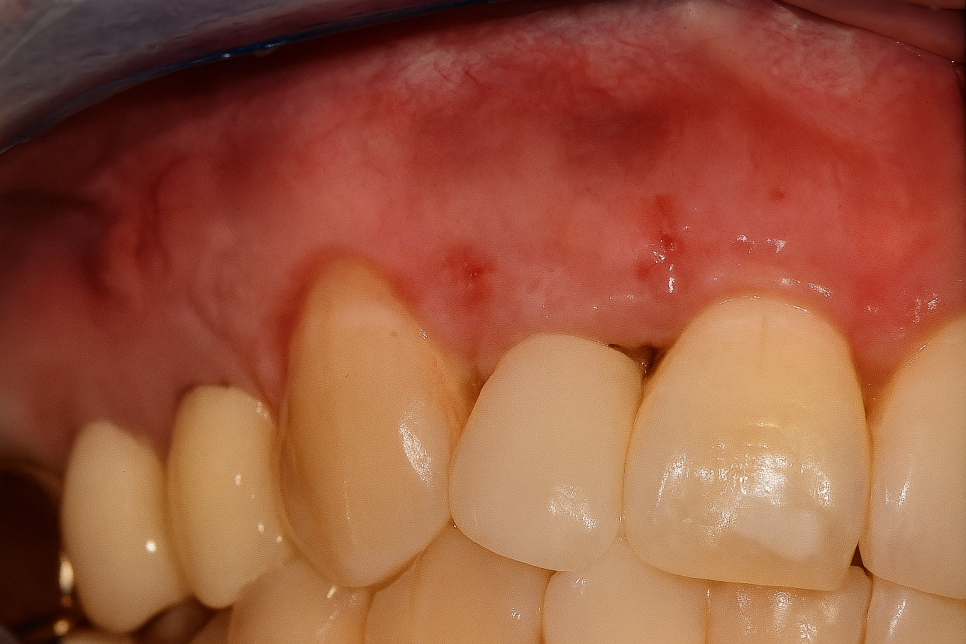

사진을 보시면 잇몸에 볼록하게 여드름이

올라온 것을 알 수 있습니다.

대개 이러한 양상을 보이는 이유는

치아 뿌리에 커다란 염증이 생겨나

심화되면서 볼록한 여드름이

잇몸에 올라오는 것이랍니다.

염증을 긁어내 깨끗한 환경이 조성되어

점차 치유되면 당산동 치과 사진처럼

잇몸 여드름이 사라지고 다시 안정된

상태를 보여주게 됩니다.